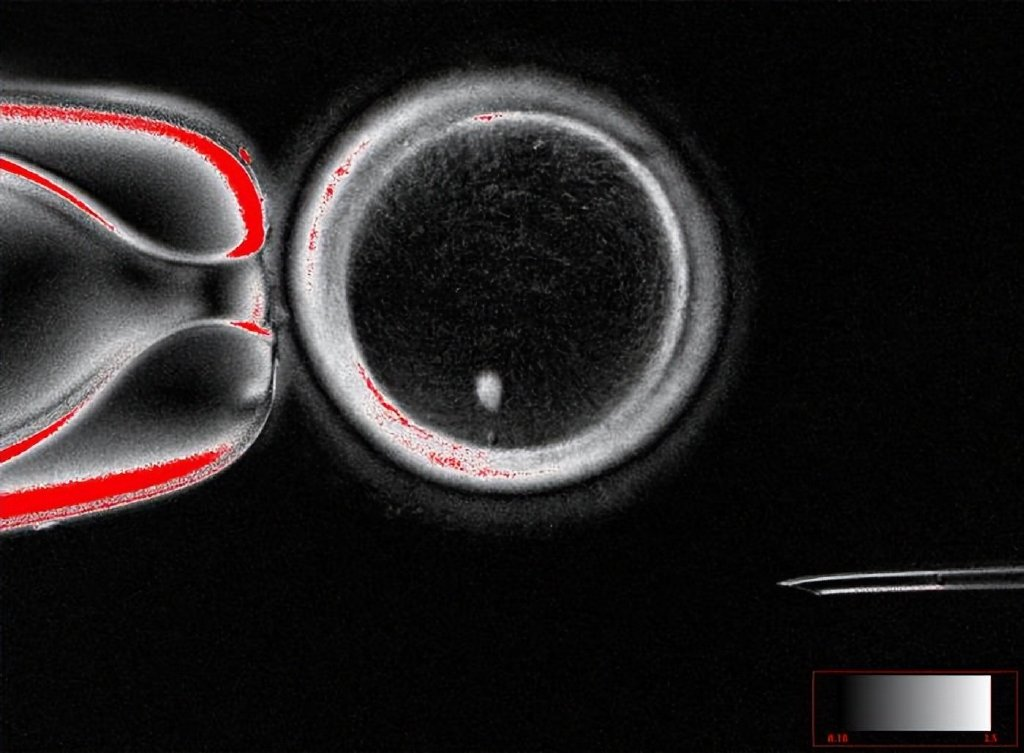

首次利用人体皮肤细胞培育出功能性卵子

近日发表于《自然-通讯》的一项研究中,科学家们首次成功将人类皮肤细胞转化为可受精的卵子,并培育出早期人类胚胎。这一概念验证研究证明了细胞重编程或是解决人类不孕症的一个可行手段,但在未来临床应用前仍需开展进一步研究确保有效性和安全性。

不孕症困扰着全球数以百万计的患者,其中许多源于她们无法产生健康的卵母细胞(卵子)。新研究首次利用人类细胞验证了这一构想(即“概念性验证”),为那些因高龄、癌症治疗或其他疾病而丧失生育能力的女性提供了一种全新的可能性——利用她们自身的体细胞(如皮肤细胞)来创造后代。

受精前卵母细胞及皮肤细胞核(亮色)。| Oregon Health & Science University

新研究的核心是一种被称为“有丝减数分裂”(mitomeiosis)的过程。研究人员首先取出捐赠者的卵子,并移除其自身的细胞核。随后他们将一个皮肤细胞的细胞核植入这个去核的卵子中。在卵子细胞质环境的诱导下,植入的细胞核会经历一次特殊的重组,抛弃其一半的染色体。这样,原本含有完整两组染色体(46条)的皮肤细胞核,就转变成了一个只含有一组染色体(23条)的单倍体细胞核,使其在遗传学上与正常配子相同。最后,这个新生成的卵子通过标准的体外受精(IVF)技术与精子结合,成功创造出发育至囊胚阶段的早期人类胚胎。

研究团队强调,这项技术目前仍处于早期实验阶段,存在许多局限,如大部分胚胎未能正常发育,并表现出染色体异常。只有约9%的胚胎成功发育到囊胚阶段。因此距离临床应用还有很长的路要走。团队预计还需要至少十年的时间来不断完善技术、验证其安全性和有效性,之后才可能考虑进入临床试验。